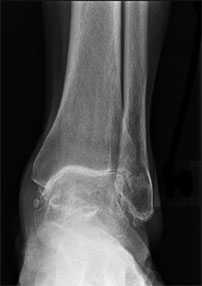

При подозрении на развитие артроза голеностопного сустава рекомендуется незамедлительно посетить врача травматолога-ортопеда. Доктор проведет осмотр и даст рекомендации относительно того, какие диагностические методики лучше всего применить. Наибольшее значение в диагностике заболевания играет рентгенография. С помощью снимков можно оценить состояние оси сустава, обнаружить вовлеченные в процесс кости и хрящи. Выполнять снимок рекомендуется с нагрузкой на ногу. Рентгенография дополнительно дает возможность понять, вовлечены ли соседние суставы и, если да, то насколько сильно процесс запущен. В некоторых случаях на основе рентгенографии можно предположить причину развития патологии.

Дополнительно может использоваться компьютерная томография и МРТ.

а. на рентгенограммах артроз голеностопного сустава, б. на КТ голеностопного сустава некроз таранной кости.